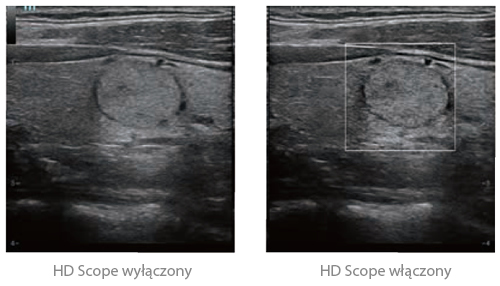

Oparta na danych kanałowych platforma ZST+ zapewnia Ulepszone Przetwarzanie Danych Kanałowych w celu uzyskania znacznie większej klarowności obrazu. Dzięki wielokrotnemu i retrospektywnemu przetwarzaniu danych kanałowych, najlepiej wykorzystuje informacje akustyczne do poprawy jakości obrazu. HD Scope: obraz o wyższej rozdzielczości w obrębie ROI (obszaru zainteresowania)

20190703155954_9762